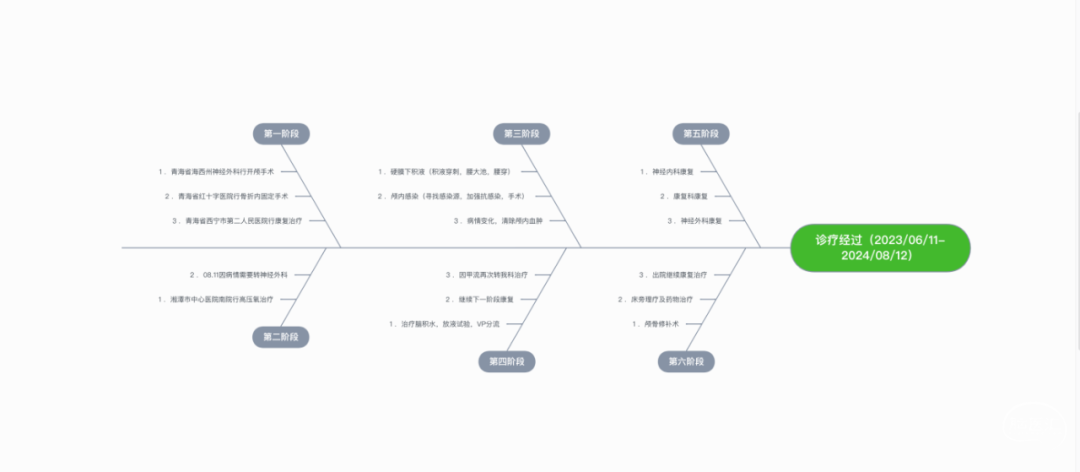

回顾既往诊疗经过

湘潭市中心医院南院骨科治疗

1. 高压氧治疗:评估有无禁忌症,于8月4日启动高压氧治疗。

2. 药物治疗:护脑、抗感染、化痰、营养支持、护肝、护胃、抗凝等治疗方案,同时动态复查血常规、肝肾功能、电解质、凝血功能,监测感染指标,定期复查痰培养。

3. 多学科会诊指导治疗:神经内科、神经外科、营养科、消化内科、高压氧舱、呼吸内科、临床药学、康复科、烧伤科、普外科会诊等。

4. 动态复查头部CT

8月21日复查CT:硬膜下积液增加,脑室扩张明显,间质性水肿加重;对患者治疗方案进行调整,转神经外科治疗。

第四阶段(多科室康复治疗)

1月28日至7月1日多个科室行康复治疗,3月26日癫痫发作一次。

第五阶段(颅骨修补术)

7月16日行PEEK材料颅骨缺损修补术。